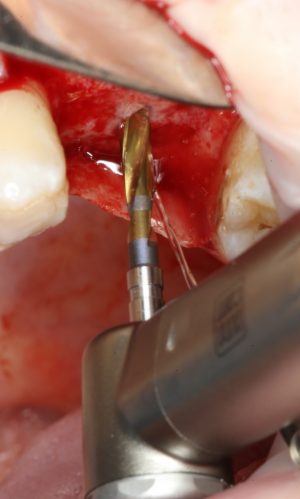

В общем, мы с вами не придурки слесари-столяры, периимплантита не хотим, поэтому кортикальные фрезы не игнорируем:

Кортикальная фреза погружается строго до отметки (см выше). В нашем клиническом случае (с синуслифтингом) это особенно важно, чтобы имплантат не улетел в субантральное пространство. Таким образом получаем лунку, полностью конгруэнтную будущему имплантату. Это очень-очень важно: